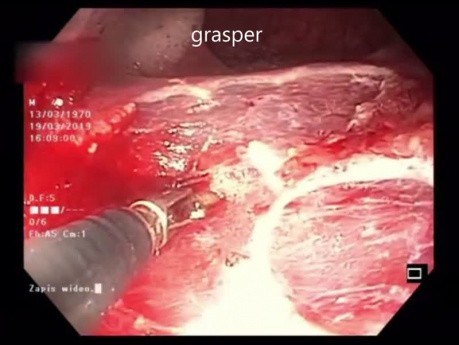

Duża zmiana o morfologii LST -G typu mieszanego...

Duża zmiana o morfologii LST-G typu mieszanego zlokalizowana 40 cm od odbytu na zagięciu z widoczną znaczną ruchomością oddechową. Zabieg rozpocęto od bocznego nacięcia. Następnie kontynuowano mukozektomię...